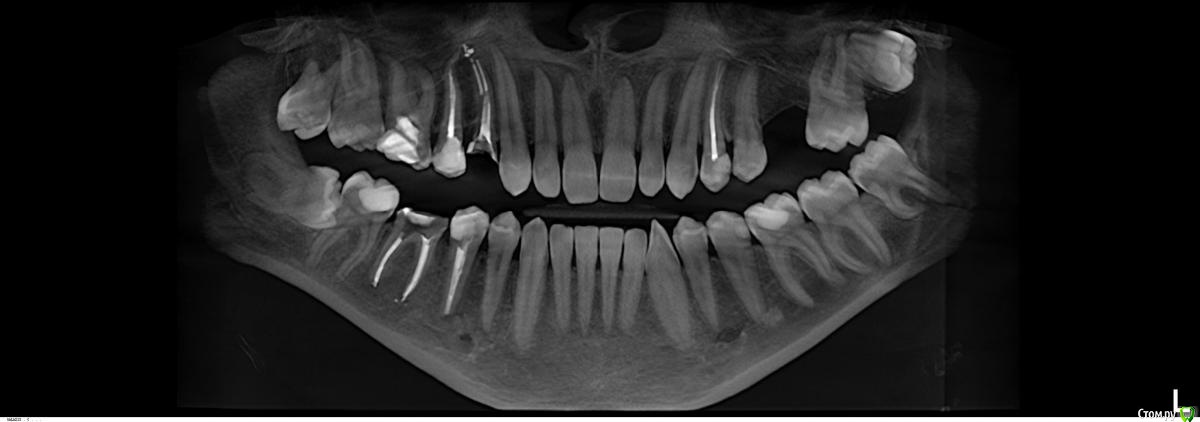

nordwinder Опубликовано 25 октября, 2018 Автор Поделиться Опубликовано 25 октября, 2018 (изменено) Прилагаю снимок. Вопрос о нижних правых 5 и 6. С верхними 4 и 5 ортопед предложил сделать так же - штифт на 5, вкладку на 4, соединенные коронки. Изменено 25 октября, 2018 пользователем nordwinder Ссылка на комментарий